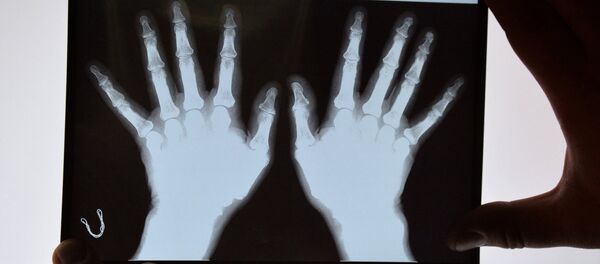

目前,用於製造植入物的常見材料為鈦和陶瓷。然而在安裝這類假體時,植入物將承受大部分載荷,從而可能造成其他骨骼的生物降解。

報道指出,俄科學家現已找到解決這一問題的方法,即採用新型材料--鈦鈮合金。這種材料的彈性模量與人類骨組織相近,適用於製造任何種類的植入物。

據消息,鈦鈮合金生產技術預計將在未來2年內問世,之後科學家將進行生物相容性測試。